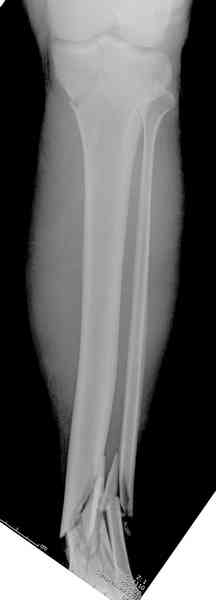

При высокоскоростных переломах редко можно встретить изолированную травму пилона, и в моей практике изолированные травмы большая редкость, поэтому, как дополнение к обсуждаемой теме, решил представить свежий, двухдневной давности случай.

Предыдущей сменой до 4:00 утра по поводу открытого перелома бедра, тибиал плато, пилон и надколенника сделана операция.

Пострадавшему 21 г., травма скоростная, после I&D с расширением раны, на бедре сделана операция ретроградным интрамедуллярным штифтом, остеосинтез с частичной резекцией надколенника и ушивание собственной связки.

На голень наружный фиксатор, рану на бедре ушили (рана была изнутри кнаружи всего 2 см). По протоколу травматических больных, до операции обследован ангиографически, (у больного дистально не смогли определить пульсацию) сосудистый хирург подтвердил проходимость на всем протяжении магистрального сосуда нижней конечности по снимкам ангиограмм.

КТ пилона имеем.